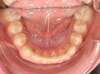

Cas N°6 : Description

Correction majeure des deux arcades dentaires liée à une mandibule rétrusive

Avant

Après